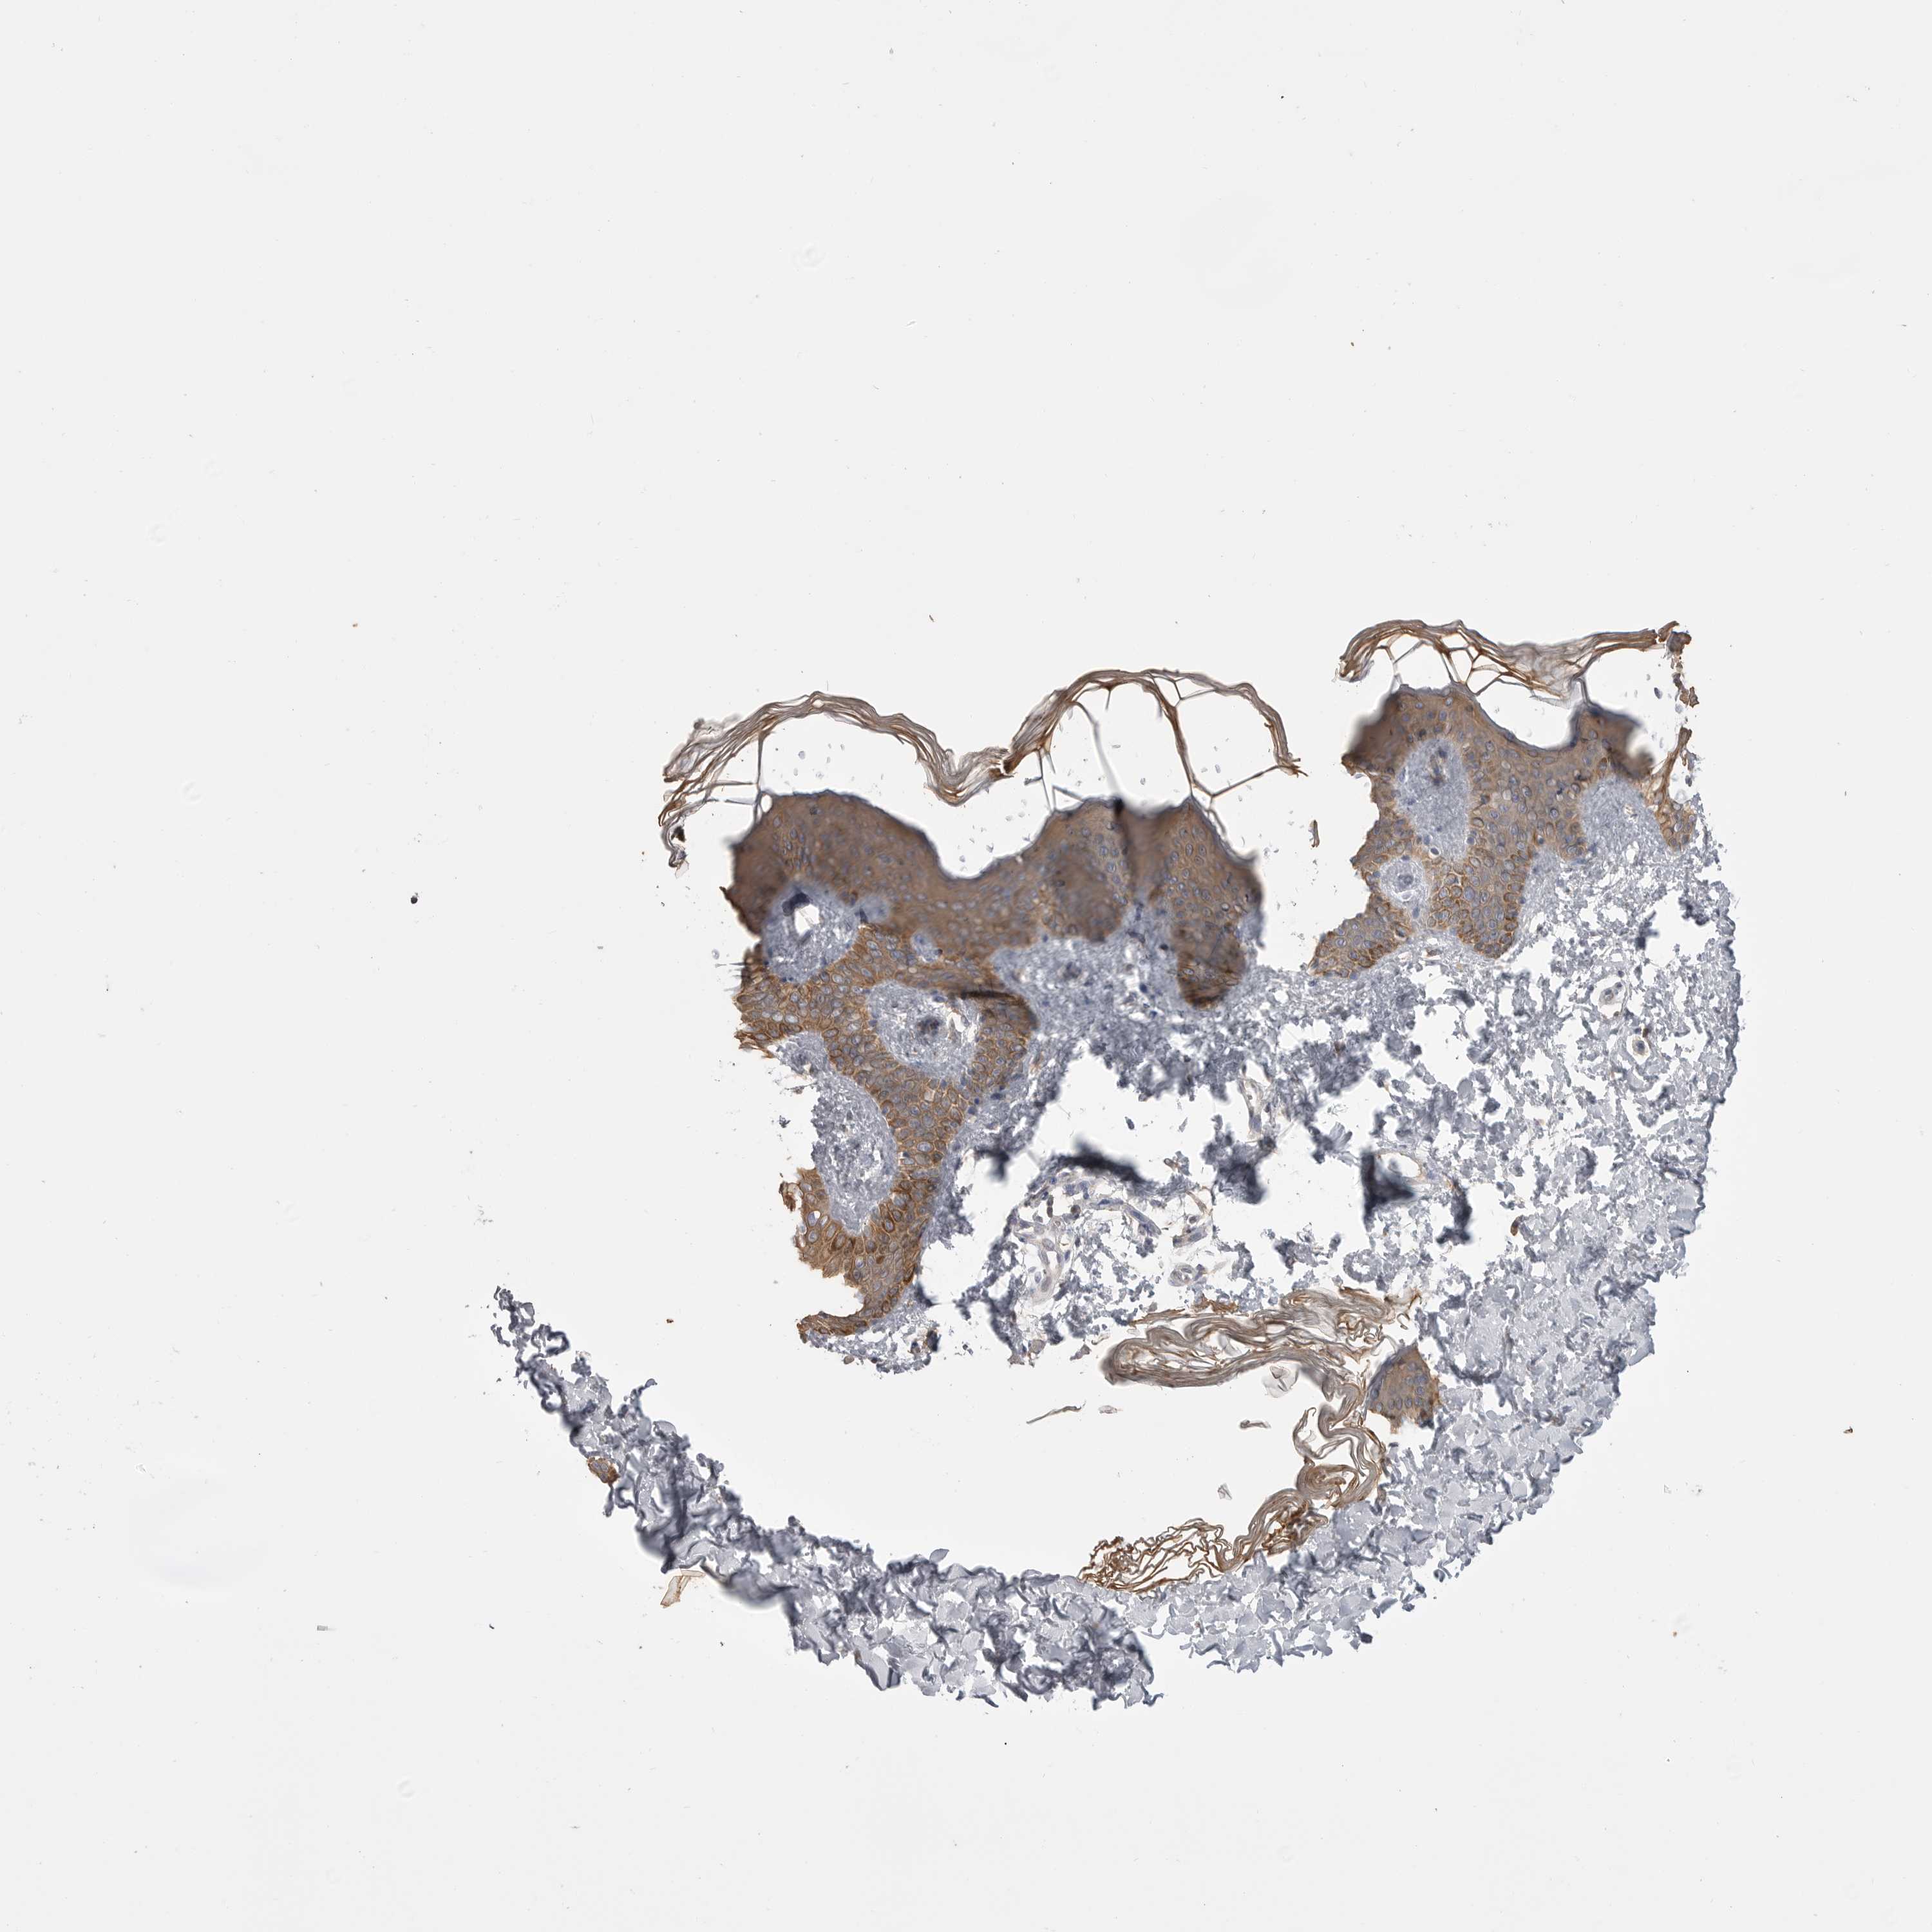

SKIN 2 - Antibody stainingi

Antibody staining in the annotated cell types in the current human tissue is reported as not detected, low, medium, or high, based on conventional immunohistochemistry profiling in selected tissues. This score is based on the combination of the staining intensity and fraction of stained cells. Each image is clickable and will lead to virtual microscopy that enables deeper exploration of all samples and also displays staining intensity scores, fraction scores and subcellular localization as well as patient and tissue information for each sample.

Antibody HPA026980

Epidermal cells Medium